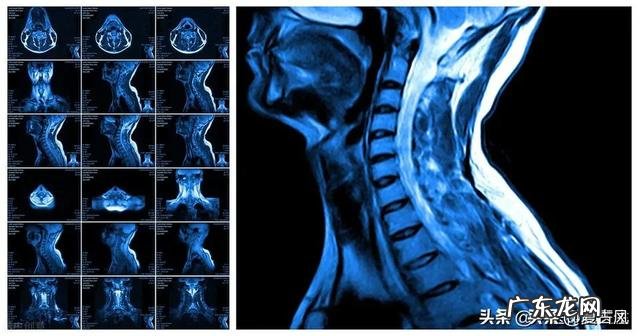

颈椎病在日常生活中越来越多 。尤其是手机电脑的普及 , 让颈椎病的发生率大幅度提高 , 而且越来越年轻化 。对于颈椎病的注意事项 , 主要有以下几点 。

第二 , 对于已经有颈椎病的患者来说 , 颈椎经常有不适 。甚至有些有头晕 , 走路不稳 , 上肢酸痛 , 麻木等等 。那么就要接受一些zhi疗 。可以到医院里配一些非甾体类的药物以及营养神经的药物 。也可以到理疗科做一些理疗 , 做一些牵引 。症状突发比较严重的 , 需要休息制动 , 也可以补液 , 甘露醇脱水甲强龙冲击 。